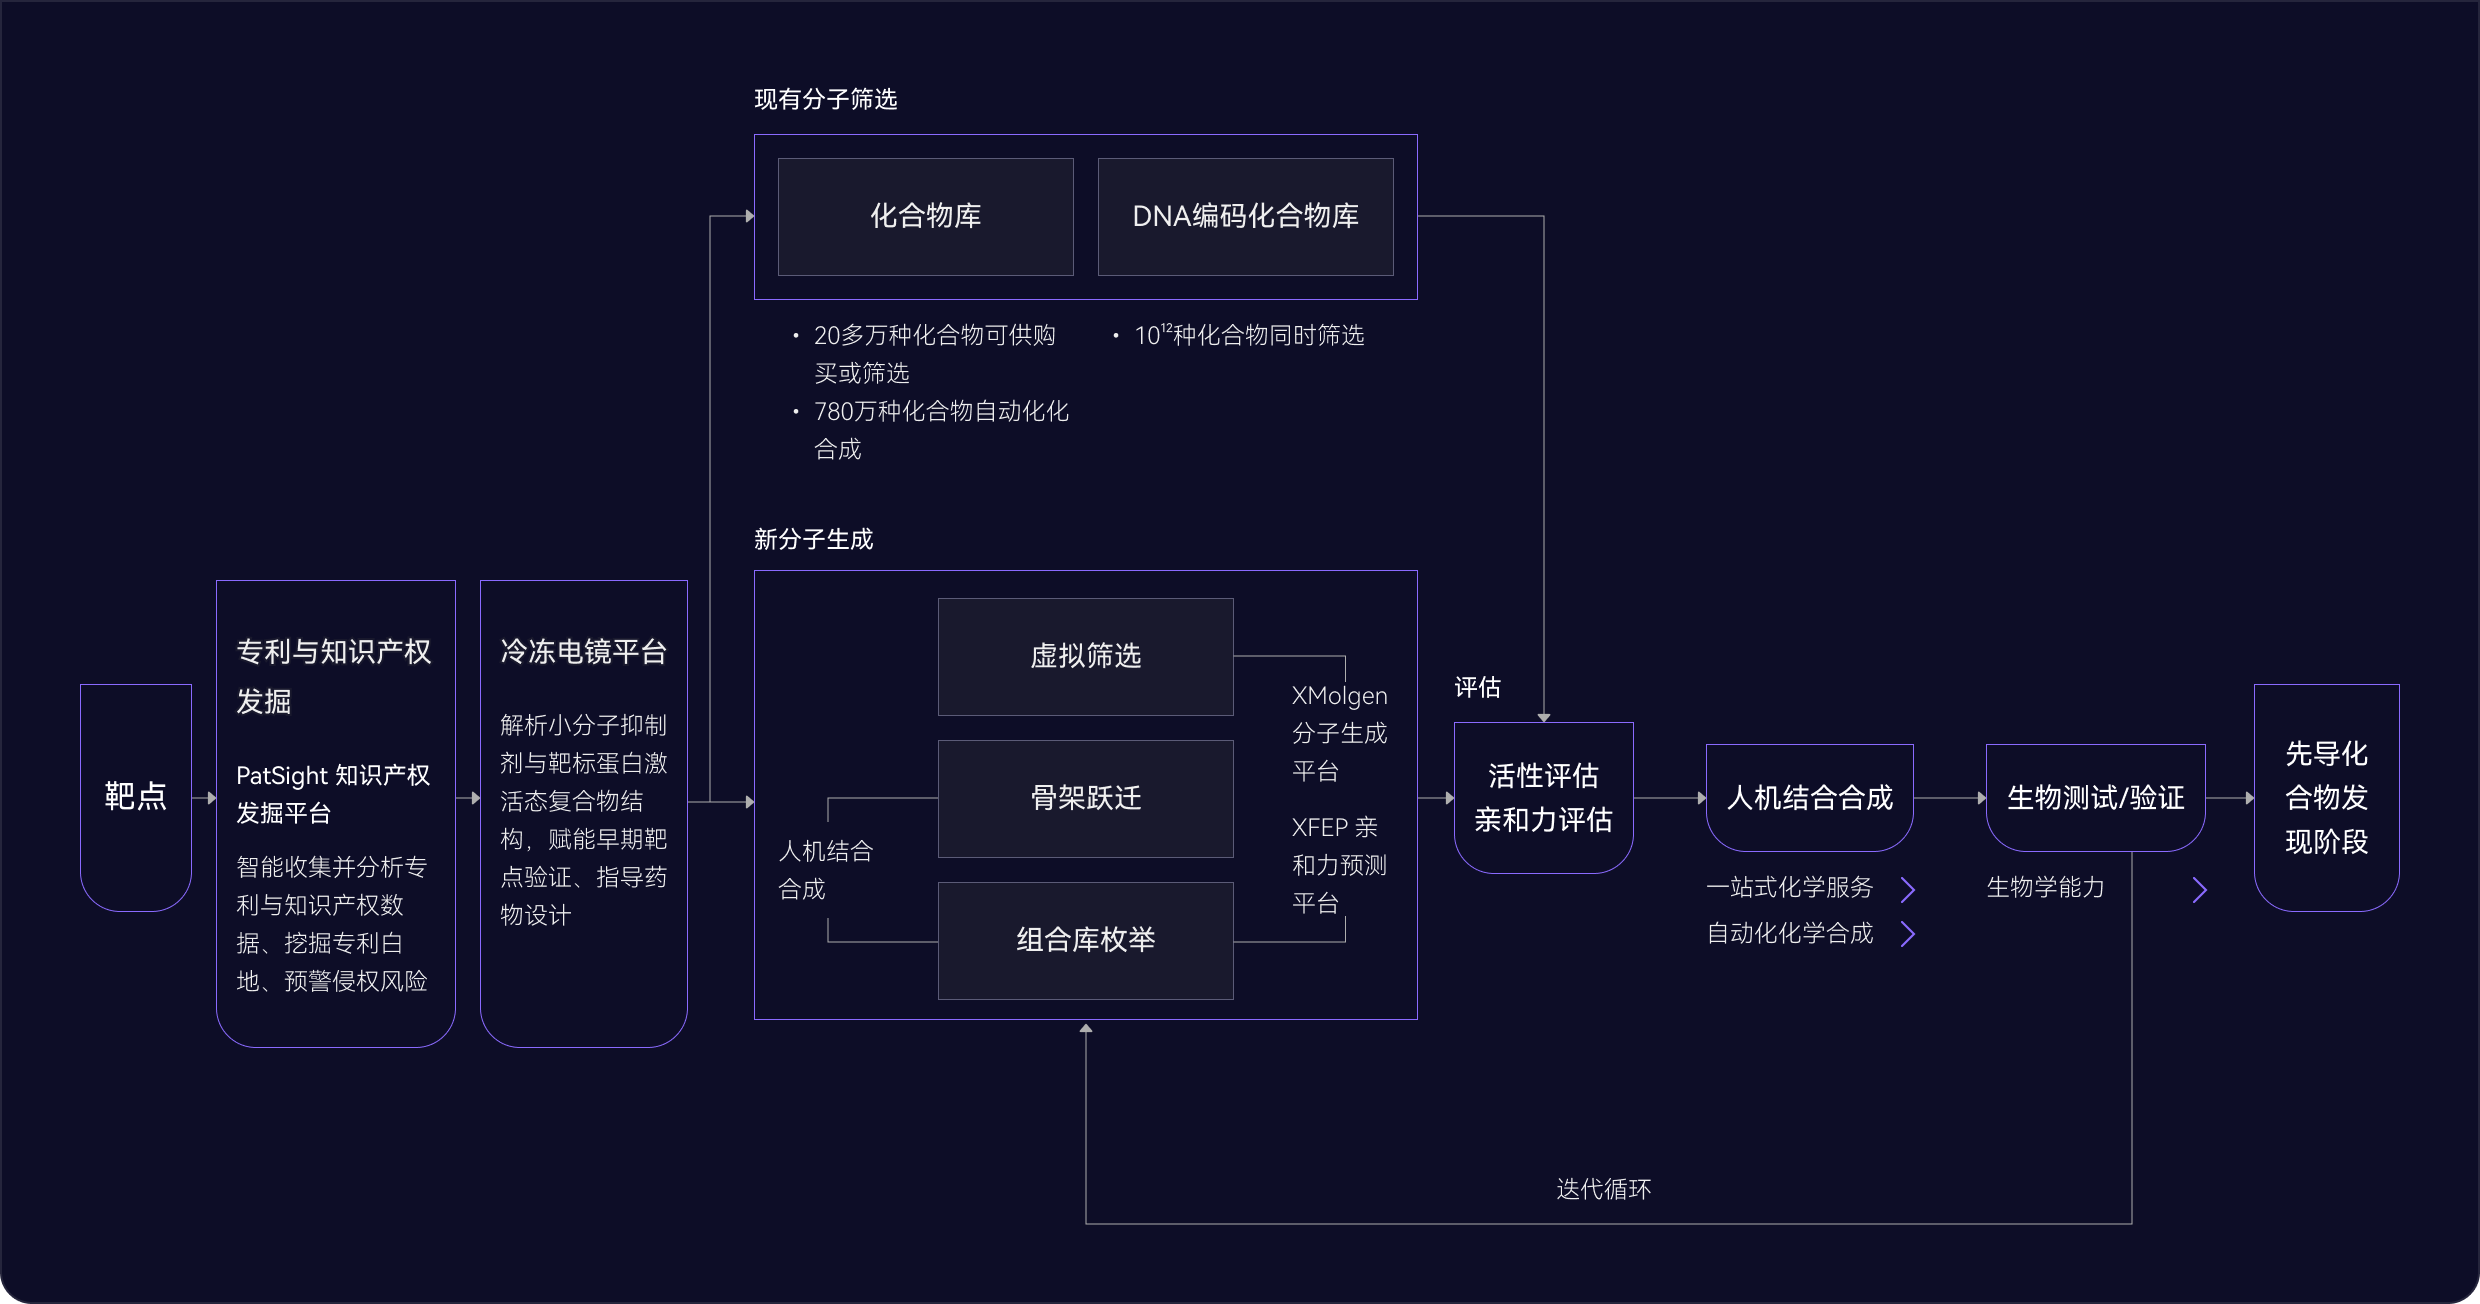

03 藥物發現平臺

ID4Inno 藥物發現平臺

04 苗頭化合物階段

多管齊下

發現最佳苗頭化合物

AI 擴展化學空間

基于AI與物理模型的有機結合,更快、更準確地探索更廣闊的化學空間,開啟您的藥物發現之旅

- 骨架躍遷和組合庫枚舉

- 200萬個分子砌塊,將化學空間擴展到1012化合物庫

- 成功為95%的項目發現苗頭化合物 (60個項目中有57個已完成)

高效藥物篩選

通過全方位的篩選,精準鎖定最具潛力的臨床前候選化合物

- 20多萬種類藥化合物可供購買或內部篩選

- 超過780萬種化合物可通過自動化化學合成

- AI驅動的自動化平臺,實現高效的篩選和數據分析

DNA編碼化合物庫

通過廣泛的多樣性和精準篩選加速發現過程

- 可同時篩選數十億種化合物,增加發現新穎苗頭化合物的機會

- 僅需少量的目標蛋白就可進行測試開發,使早期藥物發現高效且易于實施

05 先導化合物階段

尋找最佳先導化合物

并優化成藥性質

先導化合物評估與優化

通過優化活性、選擇性和類藥性,將苗頭化合物轉化為先導化合物

- 利用生成式AI(XMolGen)進行分子和庫設計,增加骨架新穎性和化合物多樣性

- 通過先進的物理計算(XFEP)進行虛擬篩選,優化活性和類藥性

- 通過專有自動化平臺,實現快速且可靠的中間體和庫合成

AI 驅動的全流程藥物發現

全流程一體化支持

從靶點到臨床前候選全流程藥物的發現一體化解決方案